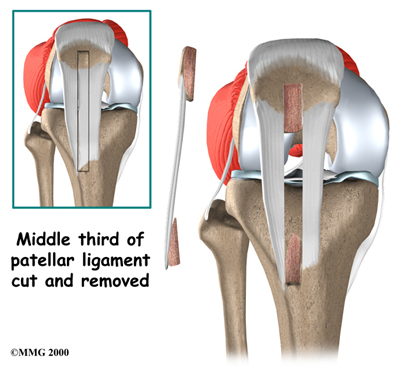

Most surgeons now favor reconstruction of the PCL using a piece of tendon or ligament to replace the torn PCL. This surgery is most often done using the arthroscope (mentioned earlier). Incisions are usually still required around the knee, but the surgery doesn't require the surgeon to open the joint. The arthroscope is used to perform the work needed on the inside of the knee joint. Most PCL surgeries are now done on an outpatient basis, and most patients stay either one night in the hospital, or they go home the same day as the surgery.

In a typical surgical reconstruction, the torn ends of the PCL must first be removed. Once this has been done, the type of graft that will be used is determined. One of the most common tendons used for the graft material is the patellar tendon. This tendon connects the kneecap (patella) to the tibia.

About one third of the patellar tendon is removed, with a plug of bone at either end. The bone plugs are rounded and smoothed. Holes are drilled in each bone plug to place sutures (strong stitches) that will pull the graft into place. Then holes are drilled in the tibia and the femur to place the graft. These holes are placed so that the graft will run between the tibia and femur in the same direction as the original PCL. The graft is then pulled into position using sutures placed through the drill holes. Screws are used to hold the bone plugs in the drill holes.